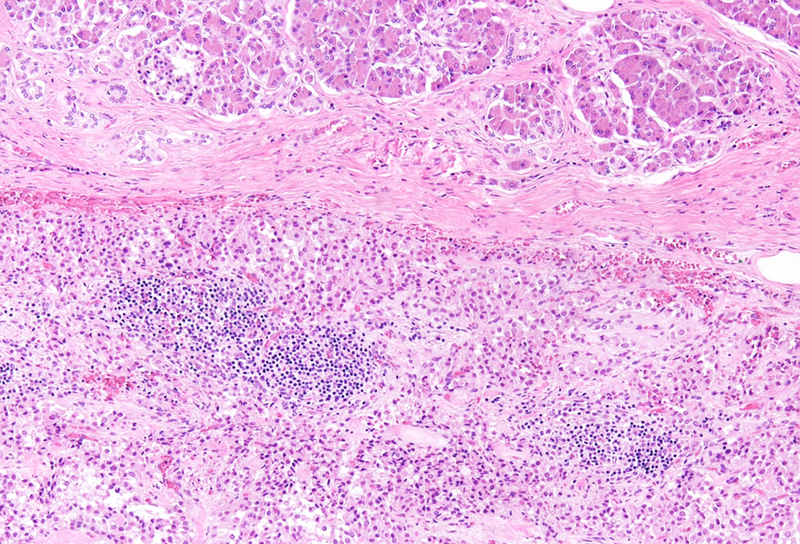

Histological examination revealed a well-circumscribed neoplasm with a fibrous capsule (Panel A), composed of uniform, poorly cohesive cells arranged in both solid (Panel B) and pseudopapillary structures (Panel C). The pseudopapillae resulted from degenerative changes leading to detachment of tumor cells from another and from central fibrovascular cores. Stromal hyalinization was also noted (Panel D). The neoplastic cells were monomorphic, with round to oval nuclei showing finely dispersed chromatin, inconspicuous nucleoli, and moderate amounts of eosinophilic to clear cytoplasm. Mitoses were not seen.